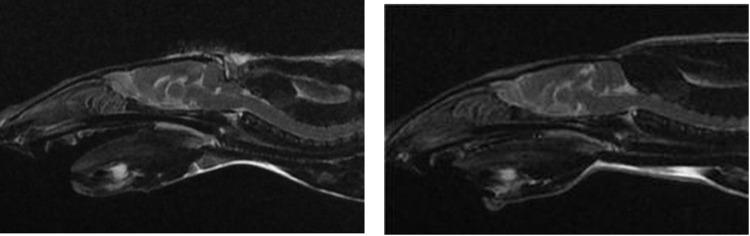

Chiari-like malformation in dogs and Chiari malformation type 1 in humans are conditions characterized by a relatively small caudal cranial fossa, leading to cerebellar herniation. This study aimed to develop a rat model of Chiari-like malformation using surgical techniques based on morphological characteristics observed in dogs.

Endocranial magnetic resonance images of both normal dogs and dogs diagnosed with Chiari-like malformation were retrospectively analyzed. Measurements of the caudal cranial fossa volume, rostral and medial fossa volume, and volume index were taken. The differences in caudal cranial fossa volume and volume index between normal dogs and those diagnosed with Chiari-like malformation were then utilized to create a rat model of Chiari-like malformation through surgical intervention. The measurements were conducted on both the rat Chiari-like malformation models and normal rats, with each measurement taken twice and the mean values calculated.

Significant differences were found between normal dogs and dogs diagnosed with Chiari-like malformation in terms of the volume of the caudal cranial fossa (27.62% reduction) and the volume index (23.36% reduction) (p<0.05). These differences were used to develop a rat model, which also showed significant reductions in both caudal cranial fossa volume (29.52%) and volume index (28.30%) compared to normal rats (p<0.05). The condition in the rat model was confirmed through magnetic resonance imaging, which revealed cerebellar herniation into the foramen magnum.

犬的 Chiari 样畸形和人类的 Chiari 畸形 I 型是一种特征为颅后窝相对较小,导致小脑疝出的疾病。本研究旨在基于犬中观察到的形态学特征,采用手术技术来建立犬 Chiari 样畸形的大鼠模型。

回顾性分析了正常犬和诊断为 Chiari 样畸形犬的颅内磁共振图像。测量颅后窝容积、颅前窝和颅中窝容积以及容积指数。然后,利用正常犬和 Chiari 样畸形犬的颅后窝容积和容积指数的差异,通过手术干预来建立 Chiari 样畸形大鼠模型。对大鼠 Chiari 样畸形模型和正常大鼠进行测量,每个测量重复两次,计算平均值。

正常犬和 Chiari 样畸形犬在颅后窝容积(减少 27.62%)和容积指数(减少 23.36%)方面存在显著差异(p<0.05)。这些差异用于建立大鼠模型,与正常大鼠相比,大鼠模型的颅后窝容积(减少 29.52%)和容积指数(减少 28.30%)也显著降低(p<0.05)。磁共振成像证实了大鼠模型的小脑疝出到枕骨大孔。